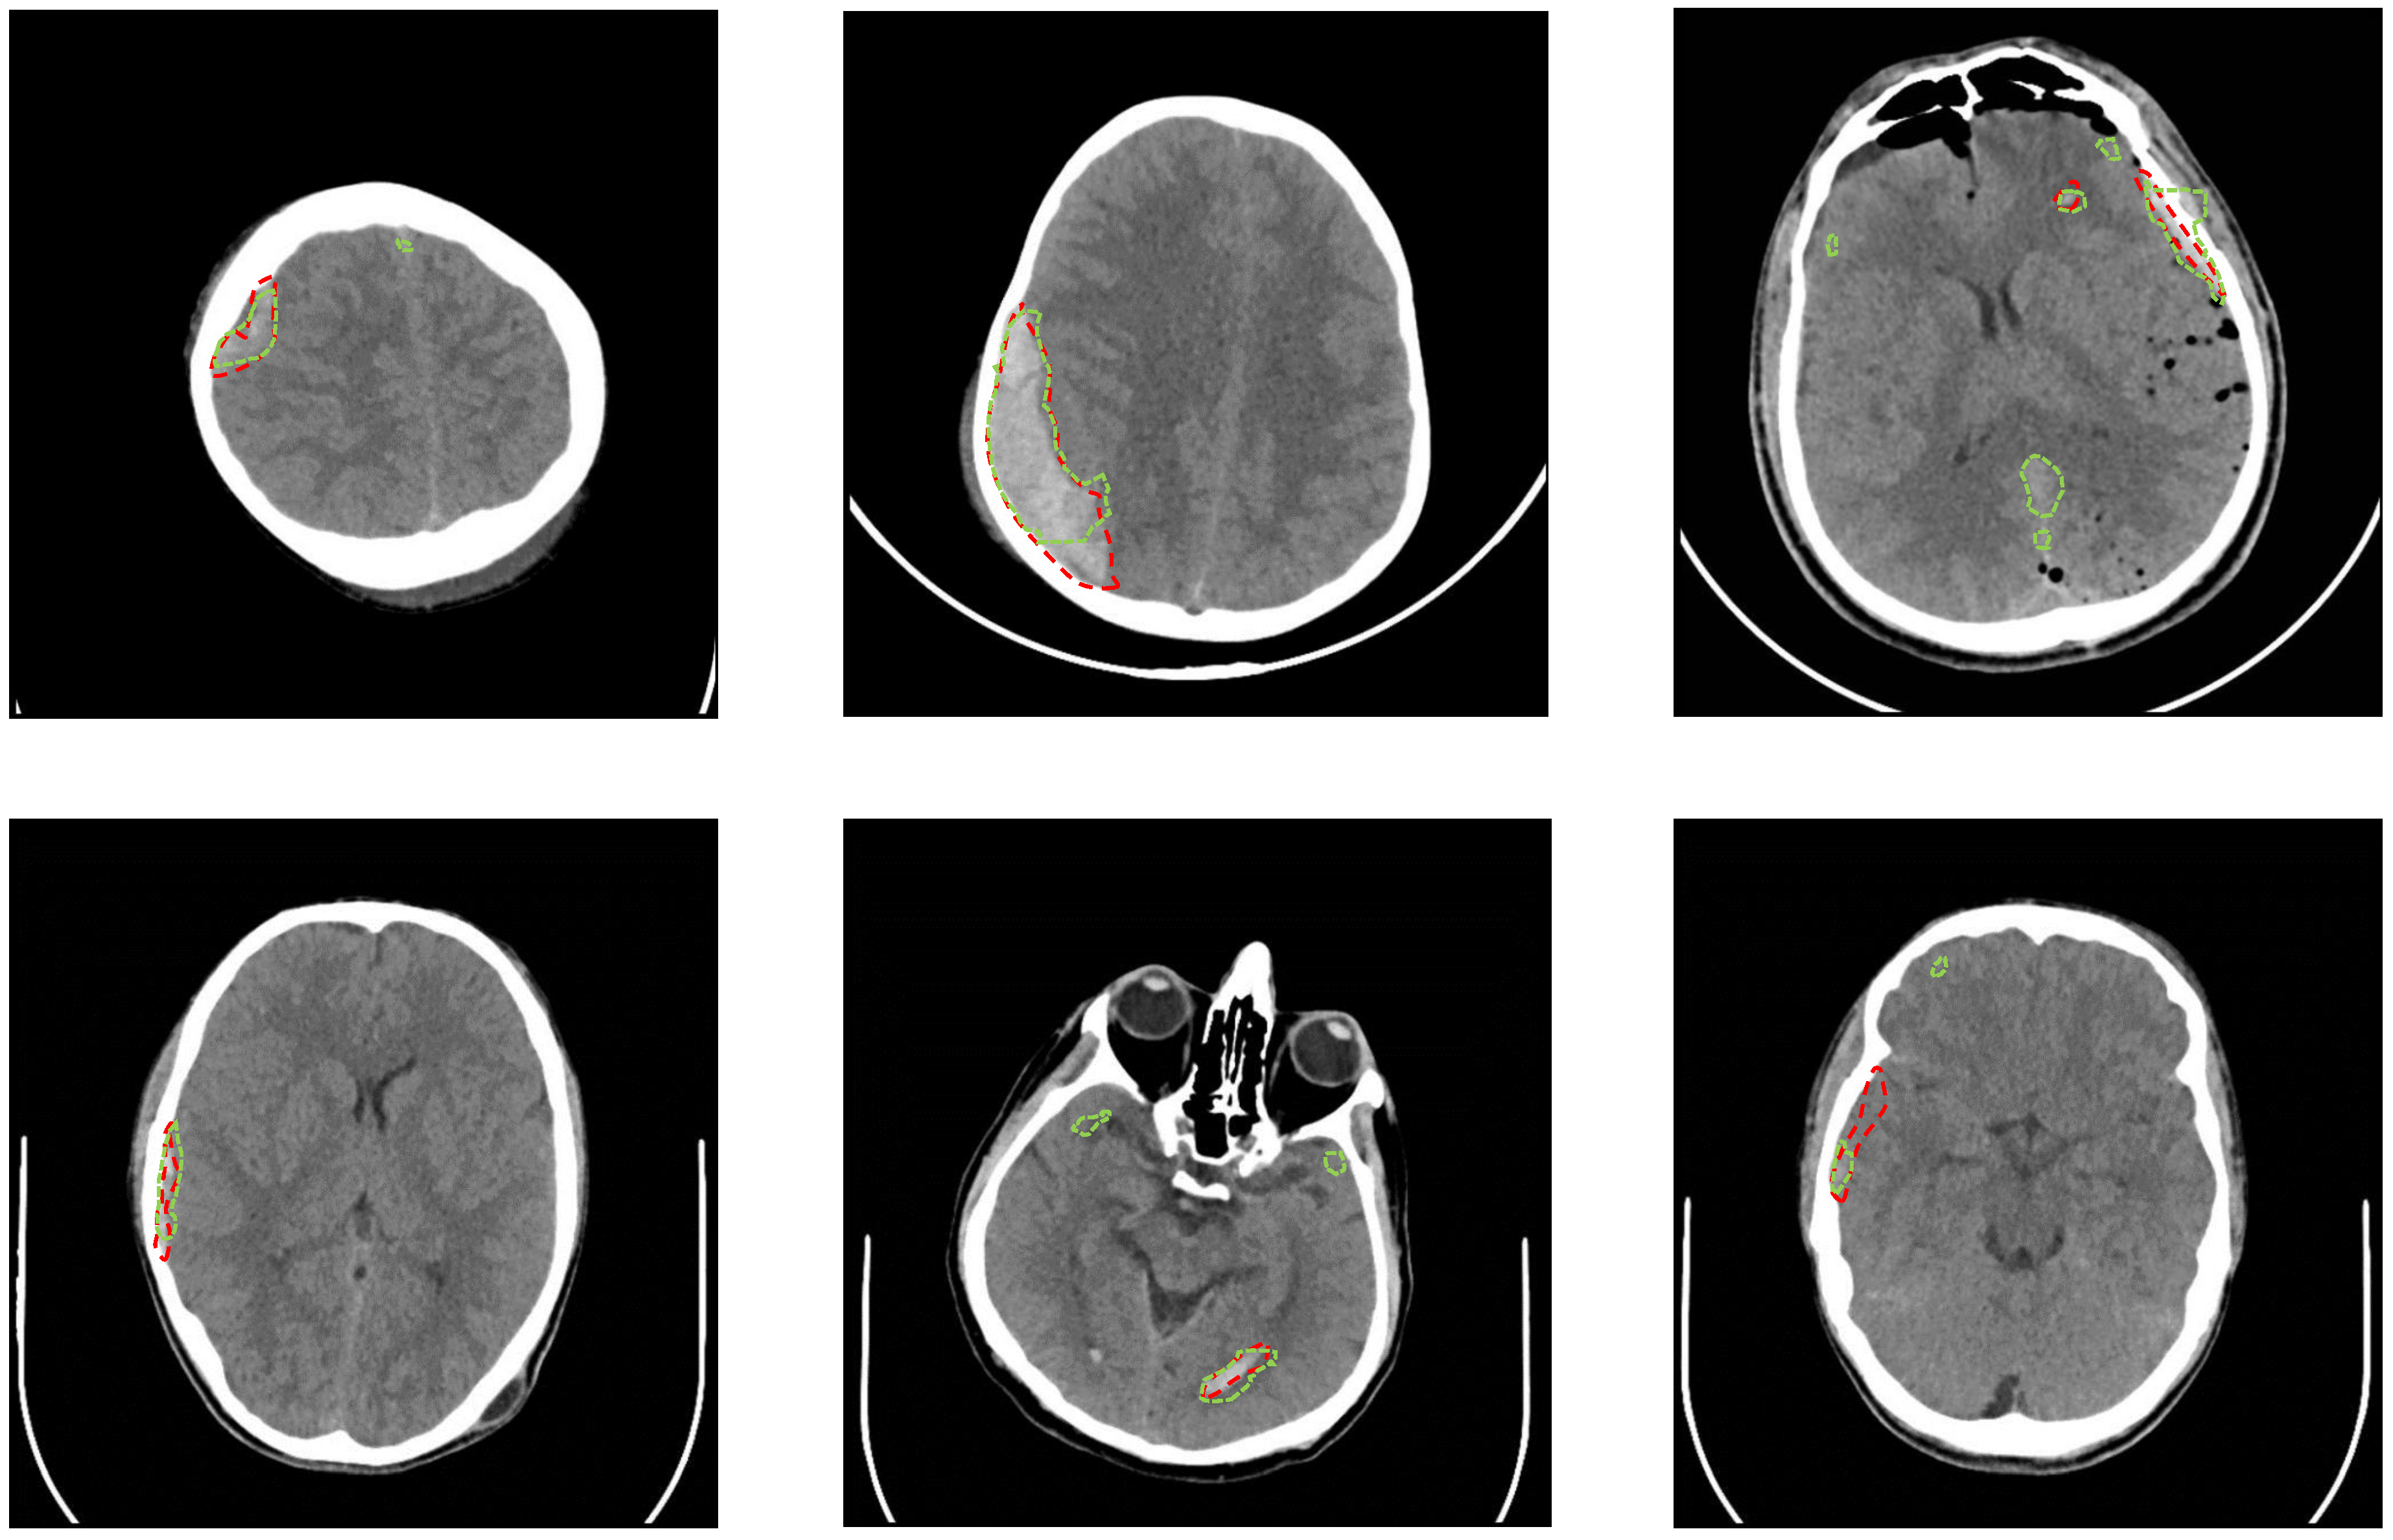

During the second experiment with the full CT slices, U-Net failed to detect any ICH regions and resulted in only black masks (i.e., negative class with no ICH). Although we used only the CT slices with an ICH, there were only a few number of ICH pixels in the dataset, which caused the model to be biased towards the negative class with no ICH. Windowing the CT slices and undersampling the negative windows in the third experiment improved the biasing issue. The 5-fold cross-validation of the developed U-Net resulted in a better performance for the third experiment as shown in Table 6. The testing Jaccard index was 0.21 and the Dice coefficient was 0.31. The slice-level sensitivity was 97.2% and the slice-level specificity was 50.4%. Increasing the threshold on the predicted probability masks yielded a better testing specificity at the expense of the testing sensitivity as shown in Table 7. Figure 4 provides the segmentation result of the trained U-Net on some test windows along with the radiologist delineation of the ICHs. The boundary effect of each predicted mask was minimal. The boundaries show low probabilities for the non-ICH regions instead of zero, and they were zeroed out after thresholding and performing the morphological operations. The final segmented ICH regions after combining the windows, thresholding, and performing the morphological operations for some CT slices are shown in Figure 5. As shown in this figure, the model matched the radiologist ICH segmentation perfectly in the slices shown on the left side, but there were some false-positive ICH regions in the right-side slices. Note that the CT slice in Figure 5, bottom right panel, shows the ending of an EDH region where it is partially segmented by the model.

Figure 4.

Samples from the windows of the testing CT slices are shown on the top. The mask or delineation of the ICH is shown with a red dotted line. The output of U-Net before thresholding and applying the morphological operations is shown on the bottom.

Figure 5.

Samples from the testing CT slices along with the radiologist delineation of the ICH (red dotted lines) and the U-Net segmentation (green dotted lines) are provided. A precise match of the U-Net segmentation is shown in the slices on the left side. There are some false-positive regions in the slices on the right side.

The results based on the ICH sub-type showed that the U-Net performed the best with a Dice coefficient of 0.52 for the SDH segmentation. The average Dice scores for the segmentation of EDH, IVH, IPH and SAH were 0.35, 0.3, 0.28 and 0.23, respectively. The minimum Dice coefficient and Jaccrad index in Table 6 was zero when the U-Net failed to localize the ICH regions in the CT scans of two subjects. One of the subjects had only a small IPH region in one CT slice, and the other subject had only a small IPH region in two CT slices. The width and height of the IPH regions for these subjects were less than 10mm, which sets the lower limit of the ICH segmentation by the proposed U-Net architecture. The results based on the subjects’ age show that the Dice coefficient of the subjects younger than 18 years old is 0.321, and it is 0.309 for the subjects older than 18. This analysis confirms that there is no significant difference between the method’s performance for the subjects younger and older than 18 years old.

One limitation of U-Net was the false-positive segmentation as shown in Figure 5, which was the main reason for the method’s low Dice coefficient. The false-positive segmentation was more prevalent near the bones, where the intensity in the grayscale image is similar to the intensity of the ICH regions. Another limitation is that the developed U-Net model failed to localize the ICH regions in the CT scans of two subjects who had small IPH regions. Hence, the current method as stands can be used as an assistive software to the radiologists for the ICH segmentation but is not yet at a precision that can be used as a standalone segmentation method. The future work can include collecting further CT scans and also enhancing U-Net with a recurrent neural network such as LSTM networks to consider the relationship between the adjacent slices when segmenting the ICH regions. Furthermore, we plan to improve the accuracy of our method by utilizing the transfer learning. The publicly available datasets for ICH detection and classification can be used for the transfer learning.